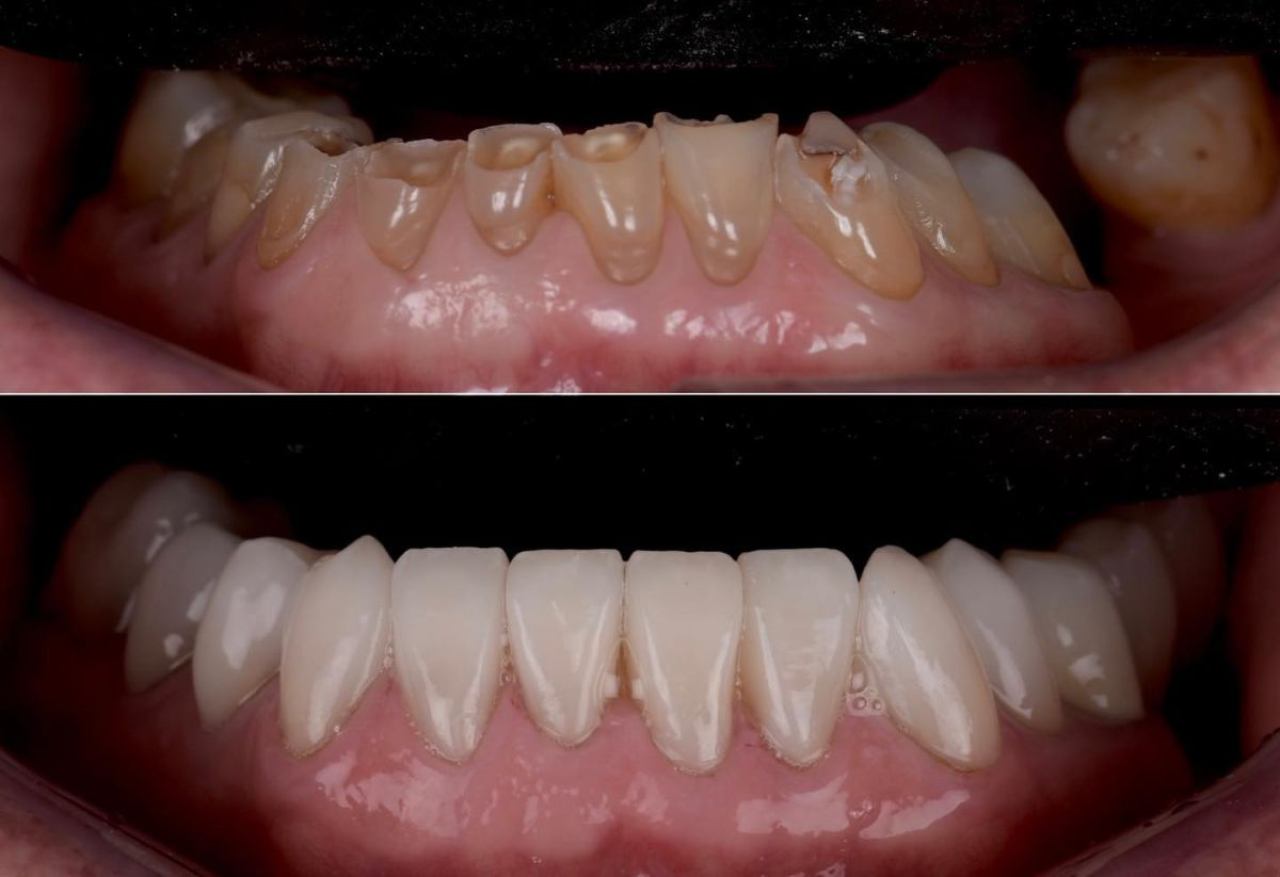

Liječenje paradontoze

Parodontitis, poznat i kao parodontoza, ne samo da može dovesti do gubitka zuba, već može imati štetne posljedice po cijelo tijelo, uključujući srce, probavni sustav, dišne puteve, dijabetes i dr.

Parodontološka terapija usmjerena je na očuvanje zdravlja potpornog aparata zuba te na umanjenje ili eliminaciju štetnih posljedica parodontitisa. Rješavanje paradontoloških problema moguće je uz paradontnu plastičnu kirurgiju, rekonstrukcijom povučenog zubnog mesa kod recesije gingive.